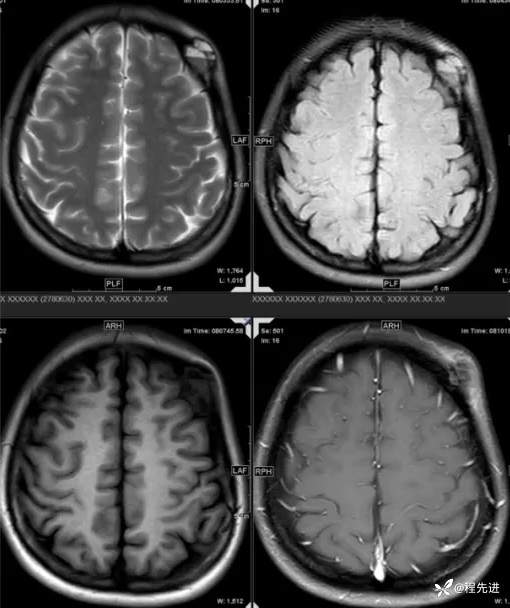

【患者信息】:女,31岁

【主诉】:发现头部肿物1月余

【现病史及既往史】:患者自诉于1月前无明显诱因出现左额颞部肿块,大小约3*3cm,伴疼痛红肿发热,遂至我院外科门诊就诊考虑“局部感染”,予以对症治疗后,肿块疼痛红肿好转,但肿块无明显缩小。

【检查】:常规检验项目均(-)